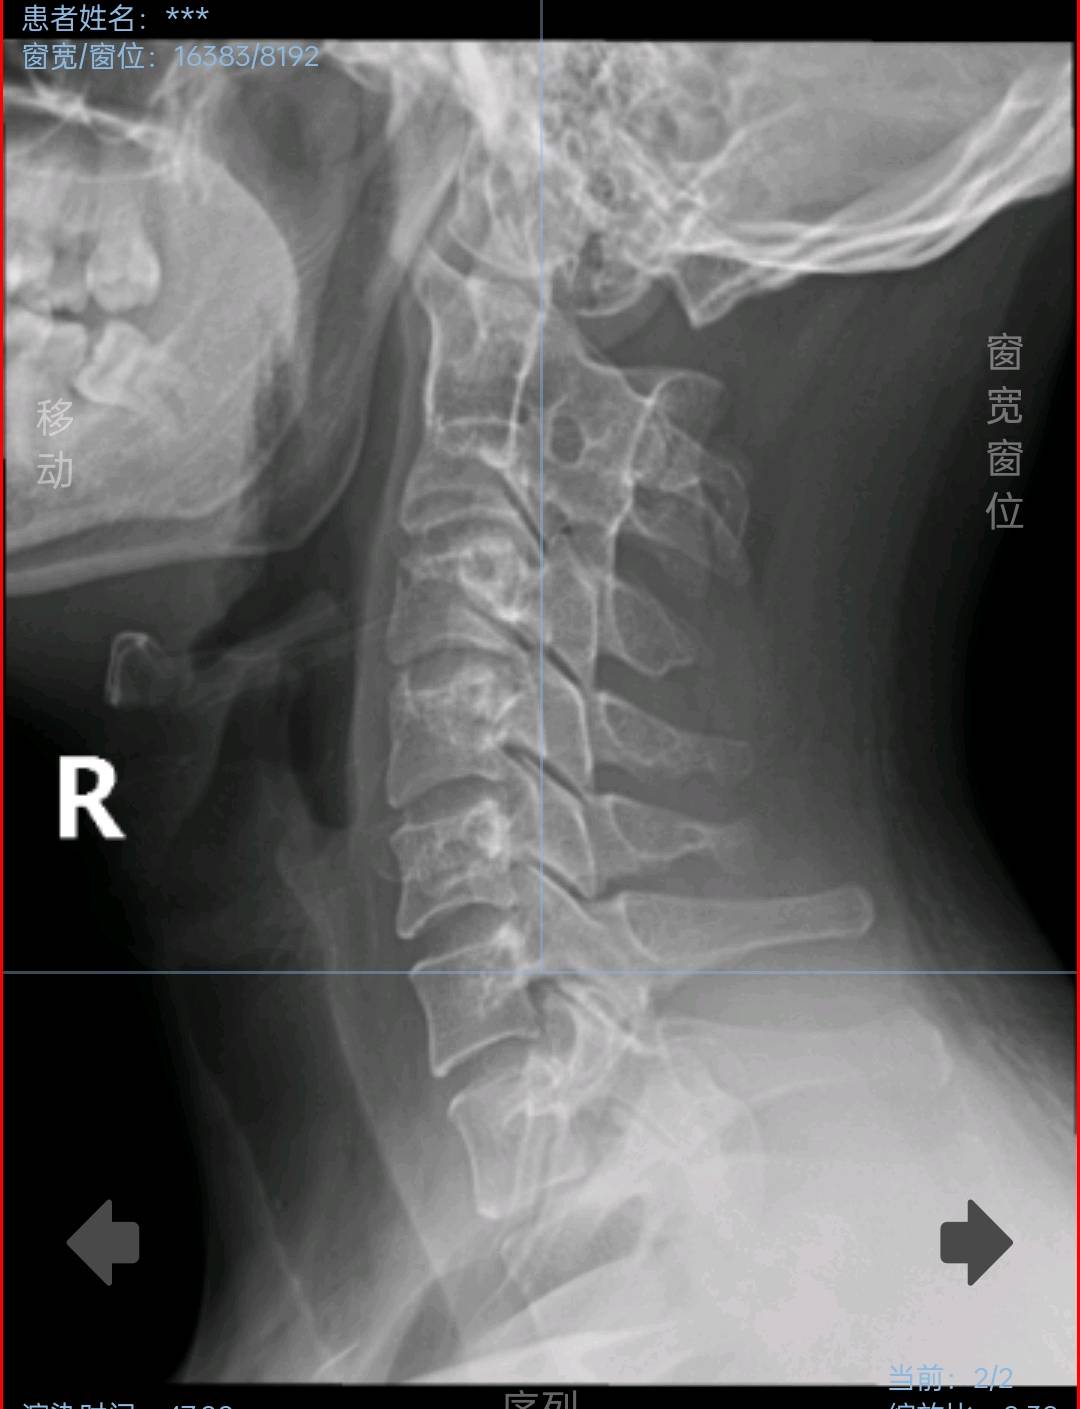

真是不拍不知道:

颈椎DR显示上位椎体分界不清,建议进一步完善颈椎CT:提示颅底凹陷,寰枕融合,上段椎体阻滞!